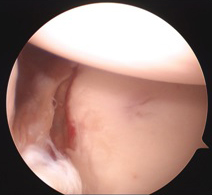

관절순 파열 수술 전